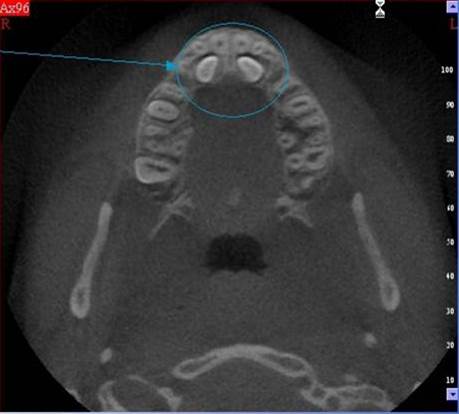

3D DVT - NewTom

Je speciální zubní digitální tříprostorový tomograf (3D), který umožňuje na základě jediného

snímkování vytvořit všechny typy RTG zobrazení, které jsou pro lékaře potřebné. Díky používané technologii tzv. „kuželového paprsku“ a speciálním senzorům je

výrazně zmenšená dávka záření - o více jak 80% proti klasickému CT vyšetření. To je významné zejména u dětí. Pomocí tohoto přístroje je možné zjisti skutečnou situaci v čelistních kostech pacienta tedy množství kosti - můžeme změřit skutečnou šířku i výšku kosti, i kvalitu kosti (hustotu) v místě uvažované implantace. 3D (tříprostorové) zobrazení umožňuje zvýšit prostorovou představu operatéra ještě před vlastní operací a zároveň pacientovi lépe objasnit a ukázat oblast plánovaného zavedení implantátu.

Pacient „neumí číst“ RTG snímky, ale díky 3D zobrazení vidí „svoji skutečnou čelist“

- např. jak je nízká či úzká, vidí průběh nervu nebo velikost čelistní dutiny, což mu umožní i pochopení nutnosti v některých případech provést pomocné zákroky ještě před vlastním zavedením implantátu (viz. kostní štěp, sinus lift, kostní granulát...).

Vyšetření pomocí tohoto přístroje používáme i ve stomatochirurgii (zlomeniny čelistí, zuby moudrosti, cysty, onemocnění čelistního kloubu), ortodoncii (retinované zuby, nadpočetné zuby), parodontologii atd.